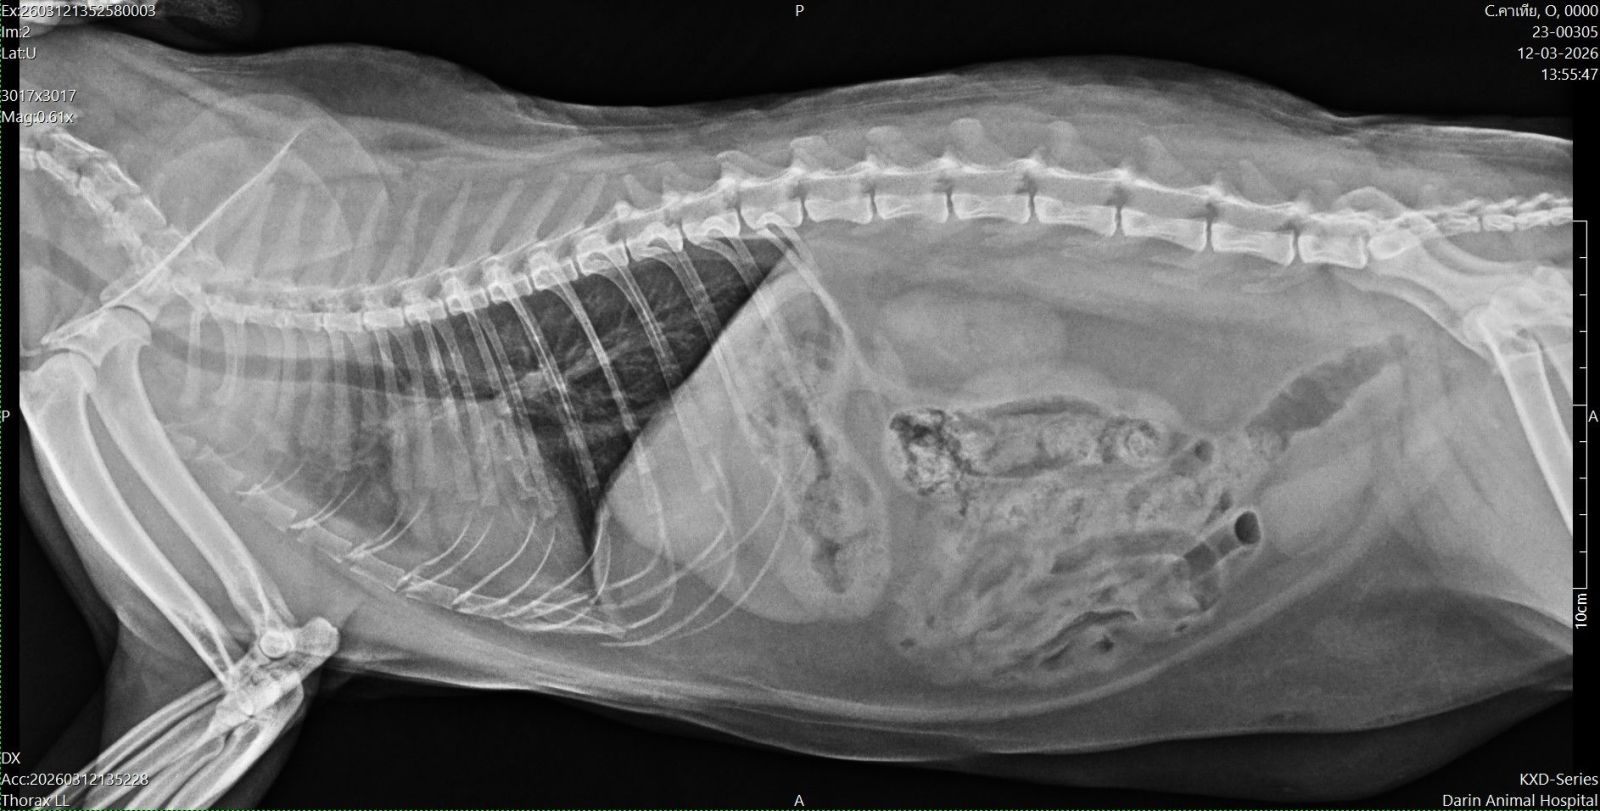

จนวันนึงถึงคราวตรวจสุขภาพประจำปี เอ็กซ์เรย์แล้วพบปอดอักเสบแบบเข้าขั้นเยอะ ถึงเยอะมากเลยล่ะ จากภาพจะมีบริเวณที่เป็นฝ้าขาว ด้านซ้ายของรูป ใต้กระดูก * คุณหมอจะอ่านภาพและชี้จุดให้ ตอนนี้ยังรอผลเลือด และวิธีการรักษาจากคุณหมอในขั้นต่อไปอยู่